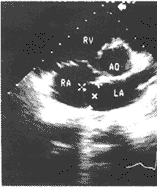

附图 二尖瓣前叶脱垂合并房间隔瘤

左:房间隔呈局限性囊状膨入右房,深13 mm,基底宽21 mm.右:同一病人二尖瓣前叶脱垂.

例1,男性,20岁。因体检发现心脏杂音来诊。查体:身材瘦长、扁平胸。胸骨左缘第二肋间及心尖区各有2/6级收缩期杂音,心尖内侧有收缩中期喀喇音。心电图TⅢ、aVF低平。X线胸片提示直背综合征。心脏彩超所见:二尖瓣前叶冗长累赘,收缩期越过瓣环突入左房伴轻度瓣返流。卵圆窝处的房间隔呈薄壁囊状于整个心动周期均膨入右房13 mm,基底部宽21 mm,未见连续回声中断或穿隔分流(附图),右心声学造影于阵咳后未见房水平分流。临床诊断:MVP合并ASA,直背综合征、心功能一级。